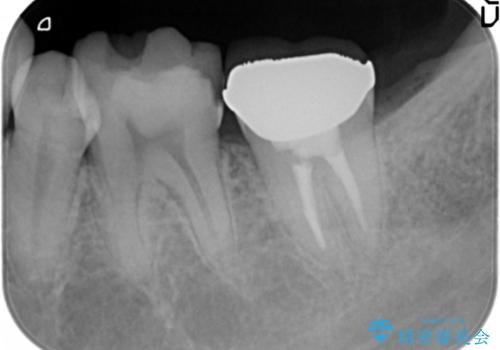

精査したところ、左下の小臼歯(左下5)が舌側転位しており、また隣の歯の詰め物は欠け虫歯になっていました。

矯正は絶対にしたくないという強いご希望により、舌側転位している歯を抜去し歯肉の治癒を待ったのち、両隣の歯の補綴治療を行いました。

セラミッククラウンにより、抜歯した部分のスペースを閉じ歯並びを整えました。